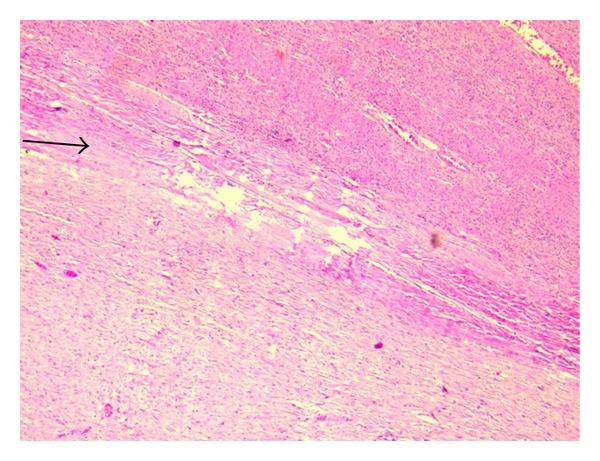

We report an unusual presentation of a sporadic intra-abdominal desmoid tumour, possibly arising from the diaphragm, masquerading as a hepatic mass in a young female without any history of surgery or trauma. Histopathology ruled out a hepatic origin of the tumour as was inferred from pre- and intraoperative evaluation. Immunohistochemistry showed positivity of lesional fibroblastic cells for β-catenin and negativity for CD34, CD117, EMA, SMA, desmin, vimentin, cytokeratin, and ALK1 thereby confirming the diagnosis of a desmoid tumour. There exist only a few reports in the literature on desmoids related to the diaphragm, but only one on a diaphragmatic desmoid that is possibly primary.

我们报告了一例散发性腹腔内硬纤维瘤的罕见表现,该肿瘤可能起源于膈肌,在一名无手术或外伤史的年轻女性中伪装成肝脏肿块。组织病理学排除了肿瘤起源于肝脏,这一点在术前和术中评估中已得到推断。免疫组织化学显示病变的成纤维细胞β-连环蛋白呈阳性,而CD34、CD117、EMA、SMA、结蛋白、波形蛋白、细胞角蛋白和ALK1呈阴性,从而确诊为硬纤维瘤。文献中关于与膈肌相关的硬纤维瘤的报道很少,而关于可能是原发性的膈肌硬纤维瘤的报道仅有一例。